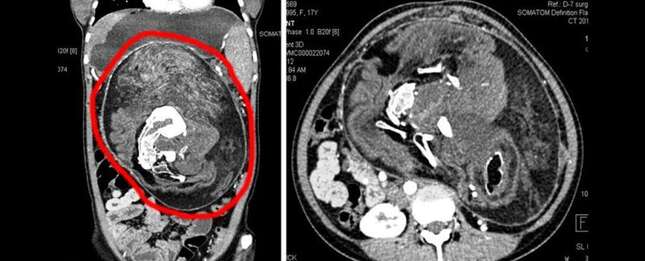

Una tomografía computarizada (CECT) con contraste abdominal mostró una masa bien definida que medía aproximadamente 25 por 23 por 15 centímetros, que se extiende desde el epigastrio [justo por encima del estómago] hasta la pelvis superior.

Mostraba áreas de densidad de grasa, tejido blando y múltiples componentes de densidad calcificada de varios tamaños y formas que se asemejan a la forma de vértebras, costillas y huesos largos. Esta masa estaba causando el desplazamiento y la compresión de las vísceras abdominales adyacentes.